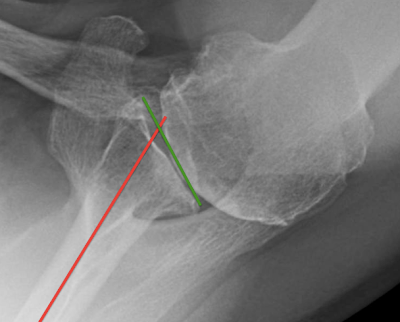

See below: the glenoid version is represented as the angle between a line connecting the anterior and posterior edges of the glenoid (green line) on one hand and a line drawn down the center of the scapular body on the other (red line).